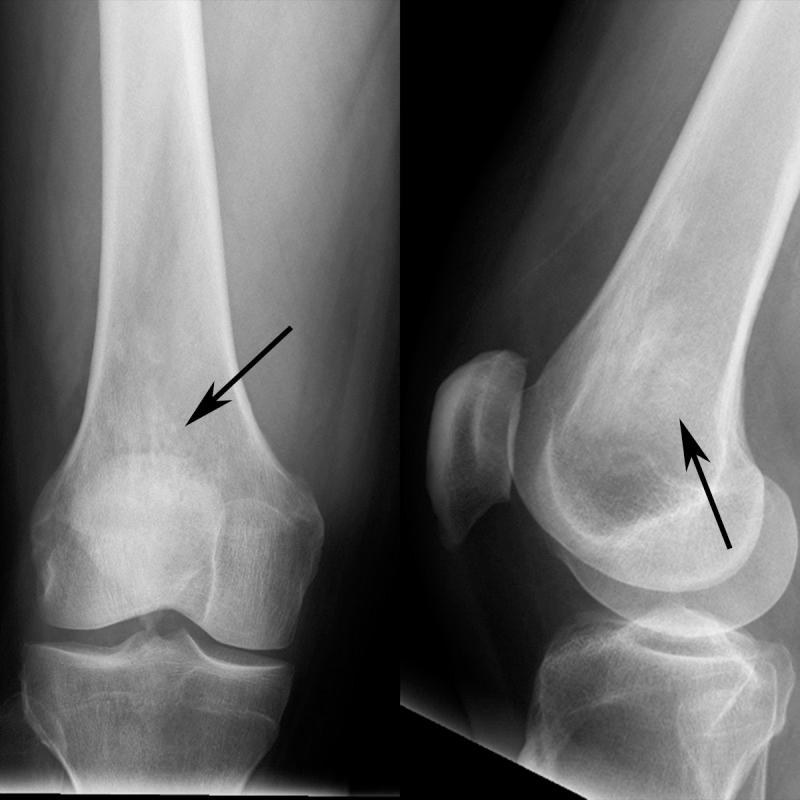

Erdheim-Chester disease (ECD) is a rare multisystemic non-Langerhans cell histiocytosis that may be clonal and inflammatory in origin. The hallmark of the disease is infiltration of various organ systems by CD68+/CD1a- histiocytes containing foamy lipid-laden inclusions. The manifestations and course of the disease are variable and depend on the organ systems that are affected. Patients may be asymptomatic or may develop life-threatening complications, including myocardial infarction. The most common clinical manifestation is lower extremity bone pain. Imaging manifestations of the disease include symmetric osteosclerosis of the distal long bones, circumferentially "coated" aorta, pleural and pericardial thickening/fluid, and perirenal encasement. Treatment for the disease is evolving, particularly with the use of molecular BRAF inhibition. We present a case of a patient with ECD initially suspected based on the imaging manifestations.

厄德里希-切斯特病(ECD)是一种罕见的多系统非朗格汉斯细胞组织细胞增多症,其起源可能是克隆性和炎症性的。该疾病的标志是含有泡沫状脂质包涵体的CD68+/CD1a-组织细胞浸润各种器官系统。疾病的表现和病程各不相同,取决于受影响的器官系统。患者可能无症状,也可能出现危及生命的并发症,包括心肌梗死。最常见的临床表现是下肢骨痛。该疾病的影像学表现包括远端长骨的对称性骨硬化、主动脉周围“包绕”、胸膜和心包增厚/积液以及肾周包裹。针对该疾病的治疗正在不断发展,尤其是使用分子BRAF抑制剂。我们报告一例最初根据影像学表现怀疑为ECD的患者病例。